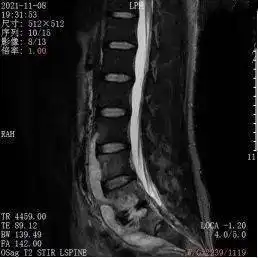

脊柱前路与后路区别 描述: 脊柱前路与后路区别 创立日期: 2025-04-28 03:25:10 图片数量: 0 pics 浏览量: 打印预览 脊柱非融合技术及其展望 天津医院小儿骨科脊柱畸形矫正策略转载 腰椎术后椎管狭窄并姿势性脊柱侧弯 青少年特发性脊柱侧弯的治疗 腰椎间盘突出腰椎间盘突出症腰椎病朋友一定要知道的 二附院实施中西部首例胸椎后路椎体opll复合物可控前移减压融合手术 腰椎滑脱,椎管狭窄症后路减压复位椎体间植骨融合术 小脚丫大健康家长必读教你选对学步鞋,为孩子打好健康基础 颈椎管狭窄前路还是后路 特色医疗脊柱结核 为什么我翘不起二郎腿也蹲不下去 新安骨科分院脊柱外科颈椎手术经典案例分享 腰椎间盘突出小常识 年轻小伙饱受脊柱结核巨大脓肿折磨,市九院专家联手祛痛除因 类别: 2025头像大全